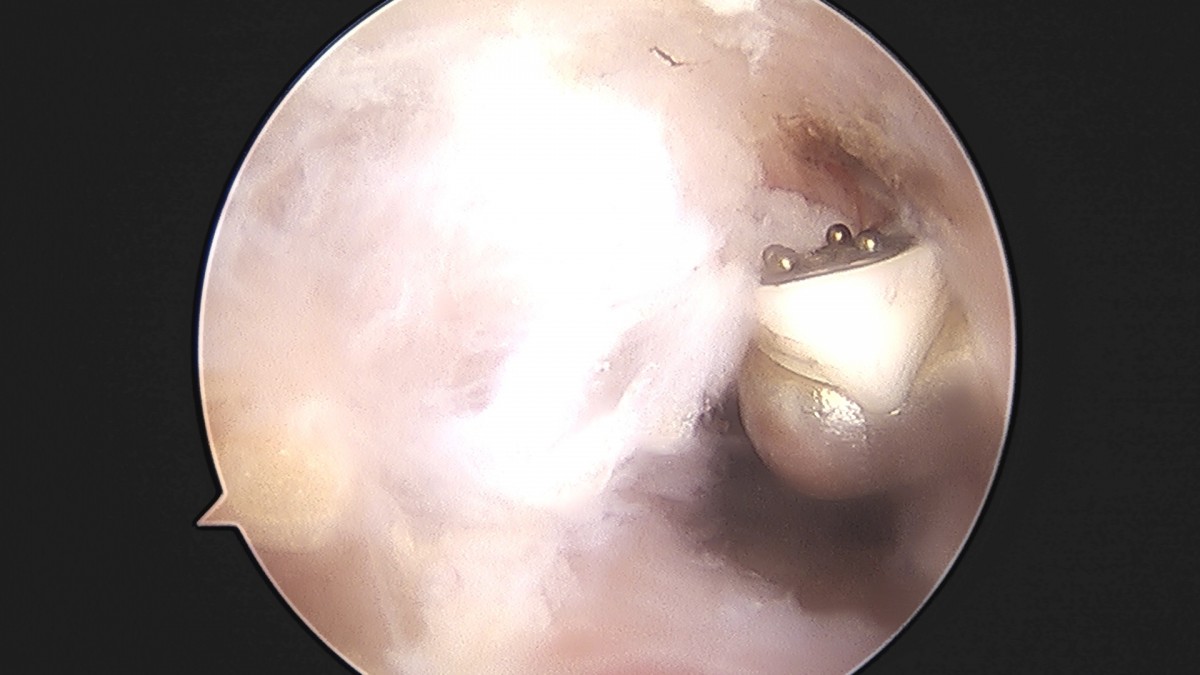

이재상원장님 어깨 견봉하 감압술 이승O 환자

작성자 최고관리자 댓글 0건 조회 806회 작성일 25-09-16 15:26